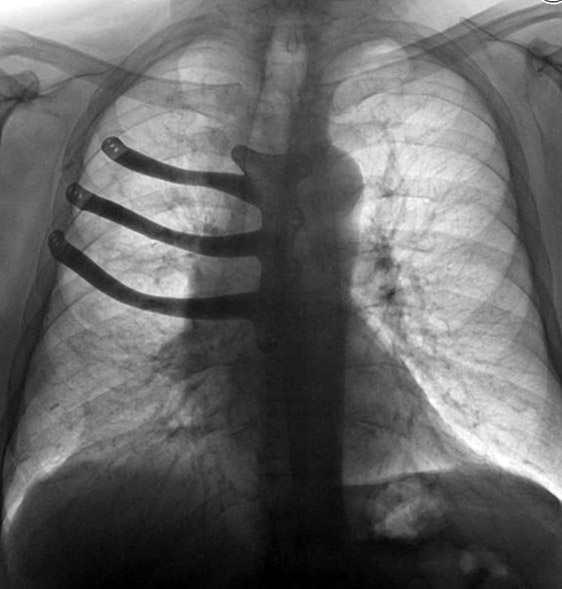

Врачи госпиталя Моррисон в британском городе Суонси реконструировали с помощью 3D-принтера грудную клетку своего пациента. 71-летнему Питеру Мэггзу из-за раковой опухоли пришлось удалить половину грудной кости и три ребра, сообщает ABMU Health Board.

Как правило, в таких случаях хирурги отливают протез из медицинского цемента во время операции, но технология 3D-печати позволила изготовить имплант из титанового сплава и сократить время операции на два часа. При изготовлении протеза использовалась компьютерная томография грудной клетки Мэггза. Это один из первых случаев печати подобных протезов в Британии.

Операция длилась восемь часов. По словам врачей, имплант сел идеально, и они планируют практиковать такое протезирование и в будущем.

Фото с сайта wales.nhs.uk